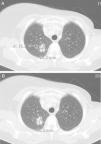

Mediante las imágenes biomédicas podemos diagnosticar, estadificar, controlar y valorar la efectividad de los procedimientos terapéuticos a los que son sometidos los pacientes oncológicos. RECIST (Response Evaluation Criteria In Solid Tumors) es el método para monitorizar el tratamiento mediante medidas unidimensionales de los tumores, obtenidas con técnicas de imagen reproducibles como son la TC, la RM y la PET. Los cambios metabólicos inducidos por los nuevos tratamientos modifican la biología y comportamiento del tumor, con discordancia ocasional entre el estado clínico del paciente y la respuesta medida con RECIST, lo que apunta a la necesidad de incluir pruebas funcionales en la valoración de la respuesta al tratamiento.

Biomedical imaging makes it possible not only to diagnose and stage cancer, but also to follow up patients and evaluate the response to treatment. RECIST (Response Evaluation Criteria In Solid Tumors) provides a method to monitor the response to treatment based on one dimensional measurements of tumors obtained with reproducible imaging techniques like CT, MRI, and PET. The metabolic changes induced by new treatments modify the biology and behavior of the tumor; occasionally, there is a discrepancy between the patient's clinical condition and the response measured by RECIST, which indicates that functional tests need to be included in the evaluation of the response to treatment.